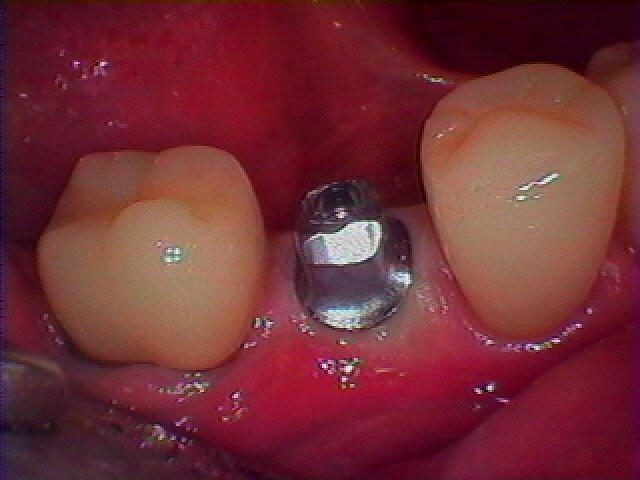

印象から2週間後、アバットメントが返ってきました

それまでに歯肉作りを行っています

アバットメントを合わせていきました